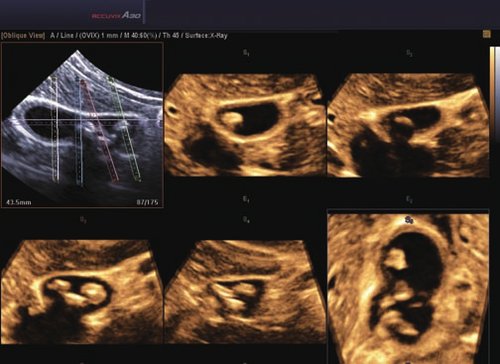

• FAD™, die Face Auto Detection, stellt das Gesicht eines Fötus besonders detailliert dar. Überflüssige Daten werden entfernt und ein besonders realistisches Bild gezeichnet.

• Volume Shade Imaging, kurz VSI™, visualisiert ein 3D-Bild, das Hauttöne und Schattierungen auf ein qualitativ neues Niveau hebt.